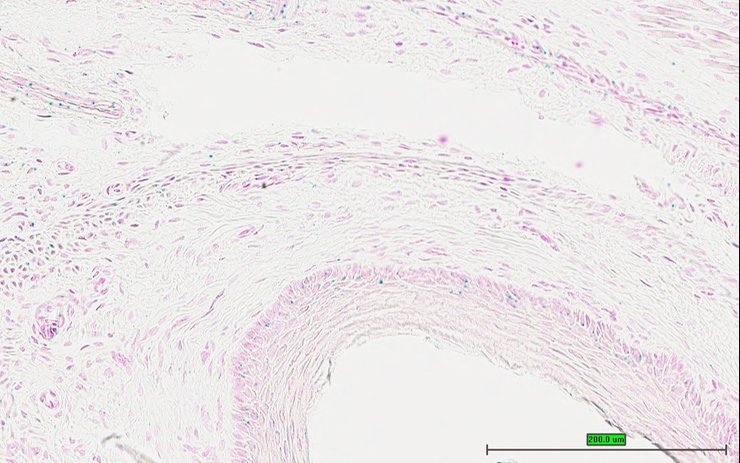

TS28: trachea Present UC Davis_1884586

Specimen UC Davis_1884587: postnatal adult; Bcs1ltm1.1(KOMP)Vlcg/Bcs1l+ (more )

TS28: trachea Present UC Davis_1884633

Specimen UC Davis_1884634: postnatal adult; Bcs1ltm1.1(KOMP)Vlcg/Bcs1l+ (more )

Structure Level Pattern Image Note

TS28: trachea Present UC Davis_1884634